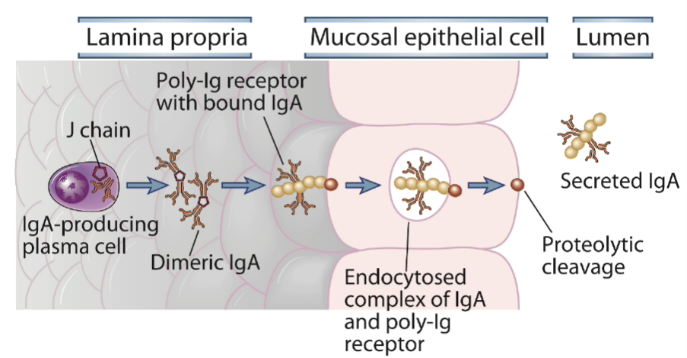

Hur sker transport av IgA genom epitel och vad ges?

B-lymfocyt utsöndrar IgA som dimerar och binder med J-kedja till receptorer på basalsidan av epitelceller varpå komplexet med receptor genom endocytos går in genom epitelcell och vid utpassering till apikalsidan klyvs komplexet och kan nu fungera som sIgA

Vilka egenskaper av sIgA?